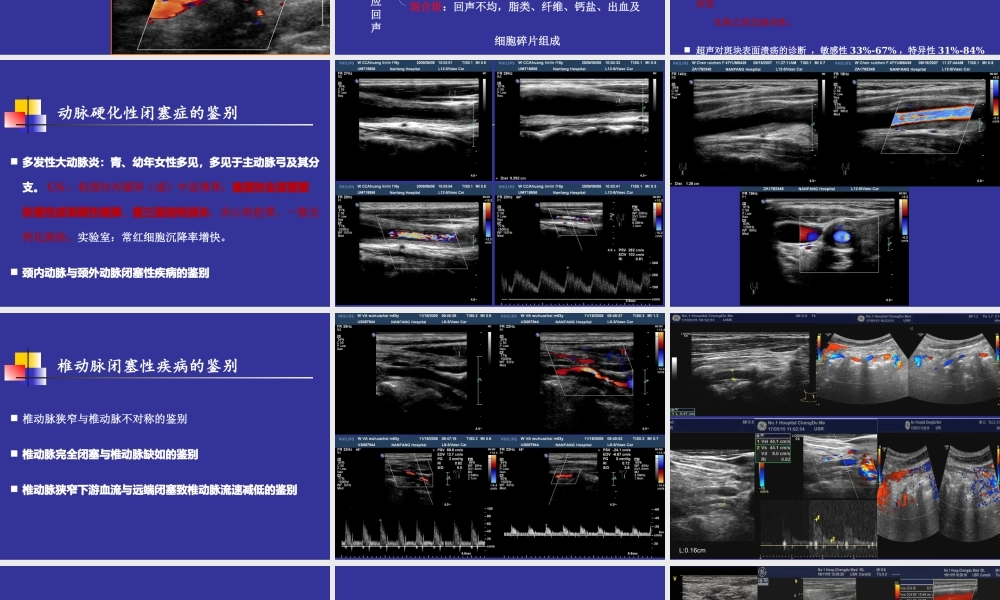

斑块的超声评价及动脉硬化性病变的鉴别(ChroniccorPulmonale)苟博颈总动脉IMT及斑块的界定内-中膜增厚:颈总IMT≥1.0mm、分叉处IMT≥1.2mm斑块:局限性IMT≥1.5mm斑块的构成:顶部(纤维帽)体部(核心部)基底部(薄的纤维帽或断裂,大的脂质核心为危险斑块)动脉粥样硬化斑块超声评价不均质回声斑块:斑块内含强、中、低回声(有超过20%面积的回声与其他部分回声不同)低回声等回声强回声动脉粥样硬化斑块超声评价根据斑块声学特征均质回声斑块扁平型溃疡型:内部回声不均质,表面有切迹,CDFI:溃疡处见“龛影”不规则型:形态不规则,凸入管腔,表面有破溃、出血或血栓附着(CDFI:斑块内见血流信号,提示出血)动脉粥样硬化斑块超声评价根据斑块形态软斑:低回声,以脂类物质为主的纤维脂肪斑块硬斑:强回声,纤维组织及钙盐沉积形成混合斑:回声不均,脂类、纤维、钙盐、出血及细胞碎片组成动脉粥样硬化斑块超声评价根据病理成分和相应回声斑块评价存在问题虽学者们广泛接受斑块回声与其构成成分之间有相关性,但超声评价斑块成分与术后斑块病理对照的相关性很差。虽然多数回顾性和前瞻性研究表明,超声观察斑块声学特征与临床症状之间具有较好相关性。但也有研究报道认为,斑块分型与脑缺血症状发生率之间无相关性。超声对斑块表面溃疡的诊断,敏感性33%-67%,特异性31%-84%多发性大动脉炎:青、幼年女性多见,多见于主动脉弓及其分支。US:轻度时外膜和(或)中层增厚;重度时全层管壁弥漫性或局限性增厚,壁三层结构消失、向心性肥厚,一般无钙化斑块。实验室:常红细胞沉降率增快。颈内动脉与颈外动脉闭塞性疾病的鉴别动脉硬化性闭塞症的鉴别椎动脉狭窄与椎动脉不对称的鉴别椎动脉完全闭塞与椎动脉缺如的鉴别椎动脉狭窄下游血流与远端闭塞致椎动脉流速减低的鉴别椎动脉闭塞性疾病的鉴别L:0.16cm锁骨下动脉盗血综合征右锁骨下动脉起始部与右无名动脉狭窄的鉴别III型与椎动脉循环阻力增大出现反向波的鉴别与胸廓出口综合征累及锁骨下动脉的鉴别锁骨下动脉盗血综合征的鉴别循环阻力增大:RI增大或舒张期反向血流,持续短III型病例: